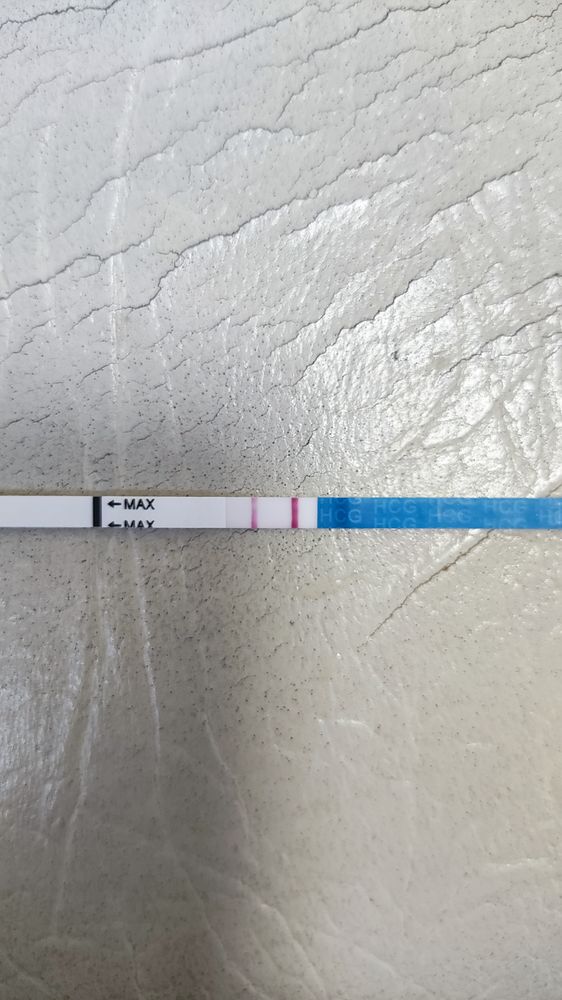

Сходила я сегодня на УЗИ. Лучше бы не ходила. В матке ничего нет. По последним М пять недель. Но факту гораздо меньше. Узистка говорит, что была поздняя овуляция. Числа 9 ПА был 7. Первая бледная полоска была 16 января. И скорее всего это был день прикрепления. Эндометрий хороший, ЖТ в левом яичнике. Я уже перепугалась за бхб. Купила эвик домой, а там почти сравнялись полосочки.